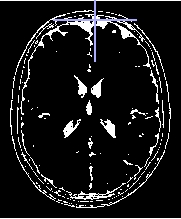

between to select all the voxels for which value of levels of gray contained between 1 and 2

Threshold1 = 391

Threshold2 = 1078